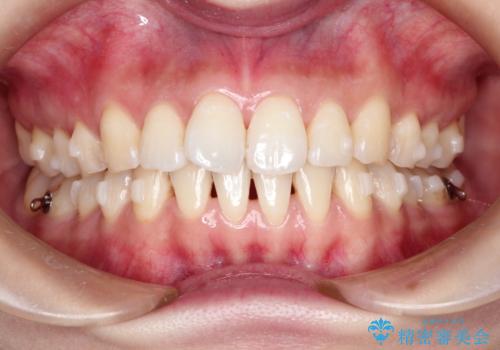

- 前歯の見た目の改善を希望され来院された患者様です。

初診時の歯並びの状態としては、上下にガタガタがある状態であり、特に上の前歯(左上1番)の捻じれを最も気にしていらっしゃいました。

口元の位置も悪くなくスペース必要量も軽度であったため、非抜歯/マウスピース矯正にて治療を行いました。

前歯の捻じれを改善するためにスペースを作る必要があり、前歯の歯の間を削って簡単に直す方法もありますが、奥歯のズレが認められたため、大臼歯後方のスペースを利用し、根本的な原因からしっかりと治療を行いました。